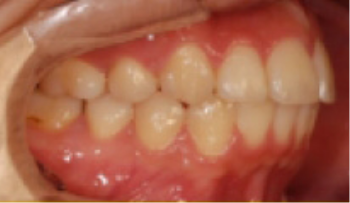

• 상악 전돌(돌출) 위턱이 앞으로 나옴.

Before

After